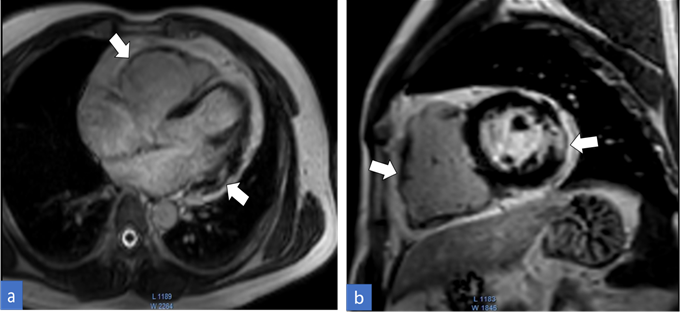

Cardiac MRI with contrast was performed for the patient on a 3Tesla platform. The CMR sequences of transverse black/bright blood images, vertical long axis, four-chamber, and short-axis cine images, left ventricular outflow tract (LVOT), right ventricular outflow tract (RVOT) views along with three-chamber cine images, and early plus delayed gadolinium enhancement sequences were obtained. The imaging findings showed dilated right atrium, right ventricle, and RVOT with irregularity of both ventricular wall (predominantly on the right side) (Figure 1). The right ventricular wall was noted to have increased trabeculations with dyssynchronous motion of the wall. Indexed end diastolic volume of the right ventricle was 120cc and the right ventricular ejection fraction (RVEF) was measured to be 32%. The delayed gadolinium images depicted diffuse enhancement in the right ventricular wall and RVOT. Patchy mid myocardial enhancement was also noted in the left ventricular wall involving the lateral segments in the basal and mid cavities (Figure 2). Mild tricuspid regurgitation with a regurgitant fraction of 16% was also noted. Based on the CMR findings and features satisfying modified task force criteria, diagnosis of ARVC with biventricular involvement was made.